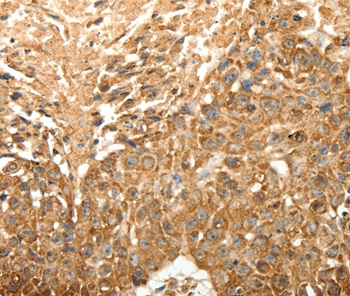

分类: 科研抗体货号: P42784别名: OGC; SLC20A4应用: WB,IHC反应种属: Human